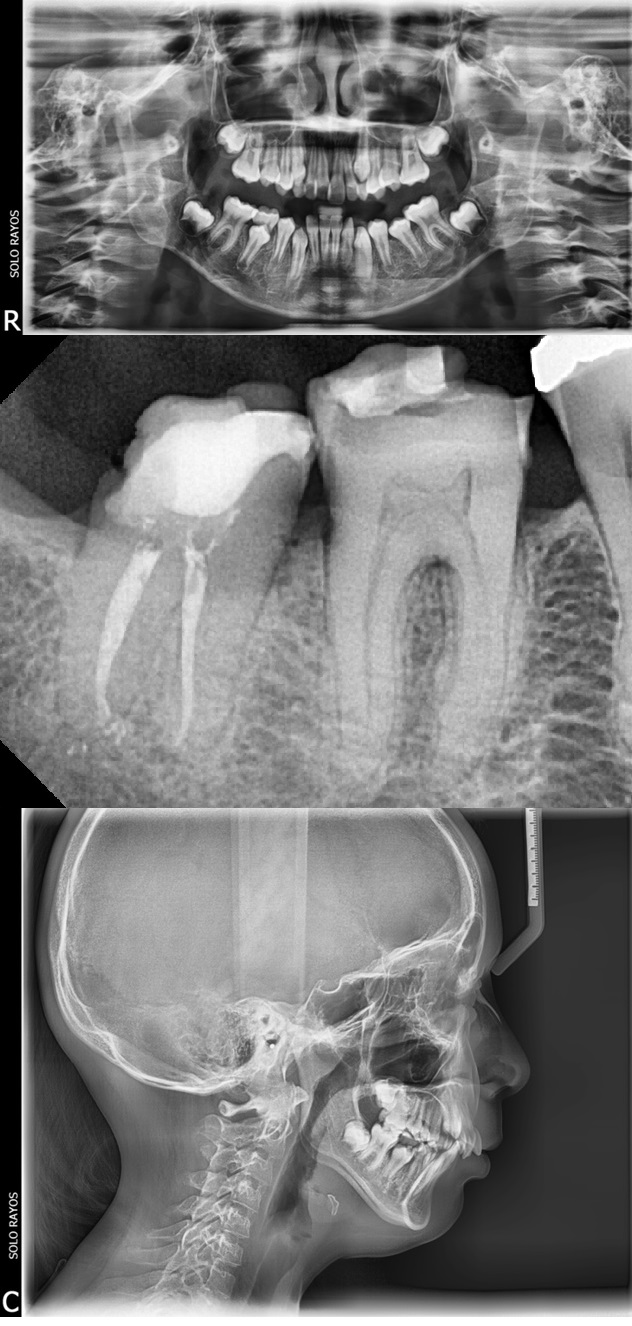

Rx Retroalveolar o Periapical

La radiografía retroalveolar es también llamada periapical y es muy útil para enfocarse en una zona determinada, porque permite evaluar en detalle el estado de dos o tres piezas dentarias

Radiografía Panorámica

Las Rx. Panorámicas requieren una máquina especial que rota alrededor de la cabeza. La radiografía captura los maxilares y los dientes completos en una sola toma. Se utiliza para planear un tratamiento para implantes dentales, verificar si hay muelas de juicio impactadas y detectar problemas mandibulares.